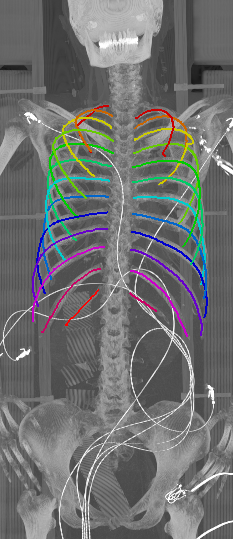

As can be seen from Table 2, we obtain overall good performance for the overall rib detection captured for example with an mean Dice of 0.84. Let us remark that for thin objects, such as the dilated rib centerlines, the Dice score constitutes a rather sensitive measure. The results indicate that detecting the first and twelfth rib pairs is more difficult for our network. While extraction of the first rib is more challenging due to, e.g., higher noise in the upper thorax or other bony structures in close vicinity (clavicle, shoulder blades, vertebrae), the twelfth rib can be extremely short and is easily confused by the neighboring ribs. For further illustration, Figure 4 shows the results on selected representative cases. Generally, the ribs are well detected without major false responses in other structures - despite all the different challenges present in the data. The color coding highlighting of the multi-label detection reveals that first and twelfth are mostly correctly detected. In few cases the network wrongly generated strong responses of the classes first rib or last rib for voxels belonging to the second or eleventh rib pair.

Refer to caption

Figure 5: Automatically generated centerline splines associated with the FCNN outputs displayed in Figure 4. The selected case above display common difficulties which are inherent in the data set, such as pads (a) or cables (b), internal devices such as pacemakers (c), stents (d), spinal (e) and femural/humeral implants (f), injected contrast agents (g), patient shape variations such as scoliosis (h), limited field of views (FOVs), i.e. partly missing first (i) or twelfth rib (j).